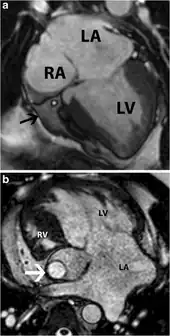

| Anterior (frontal) view of the opened heart. White arrows indicate normal blood flow. (Atresic tricuspid valve labeled at bottom left.) | |